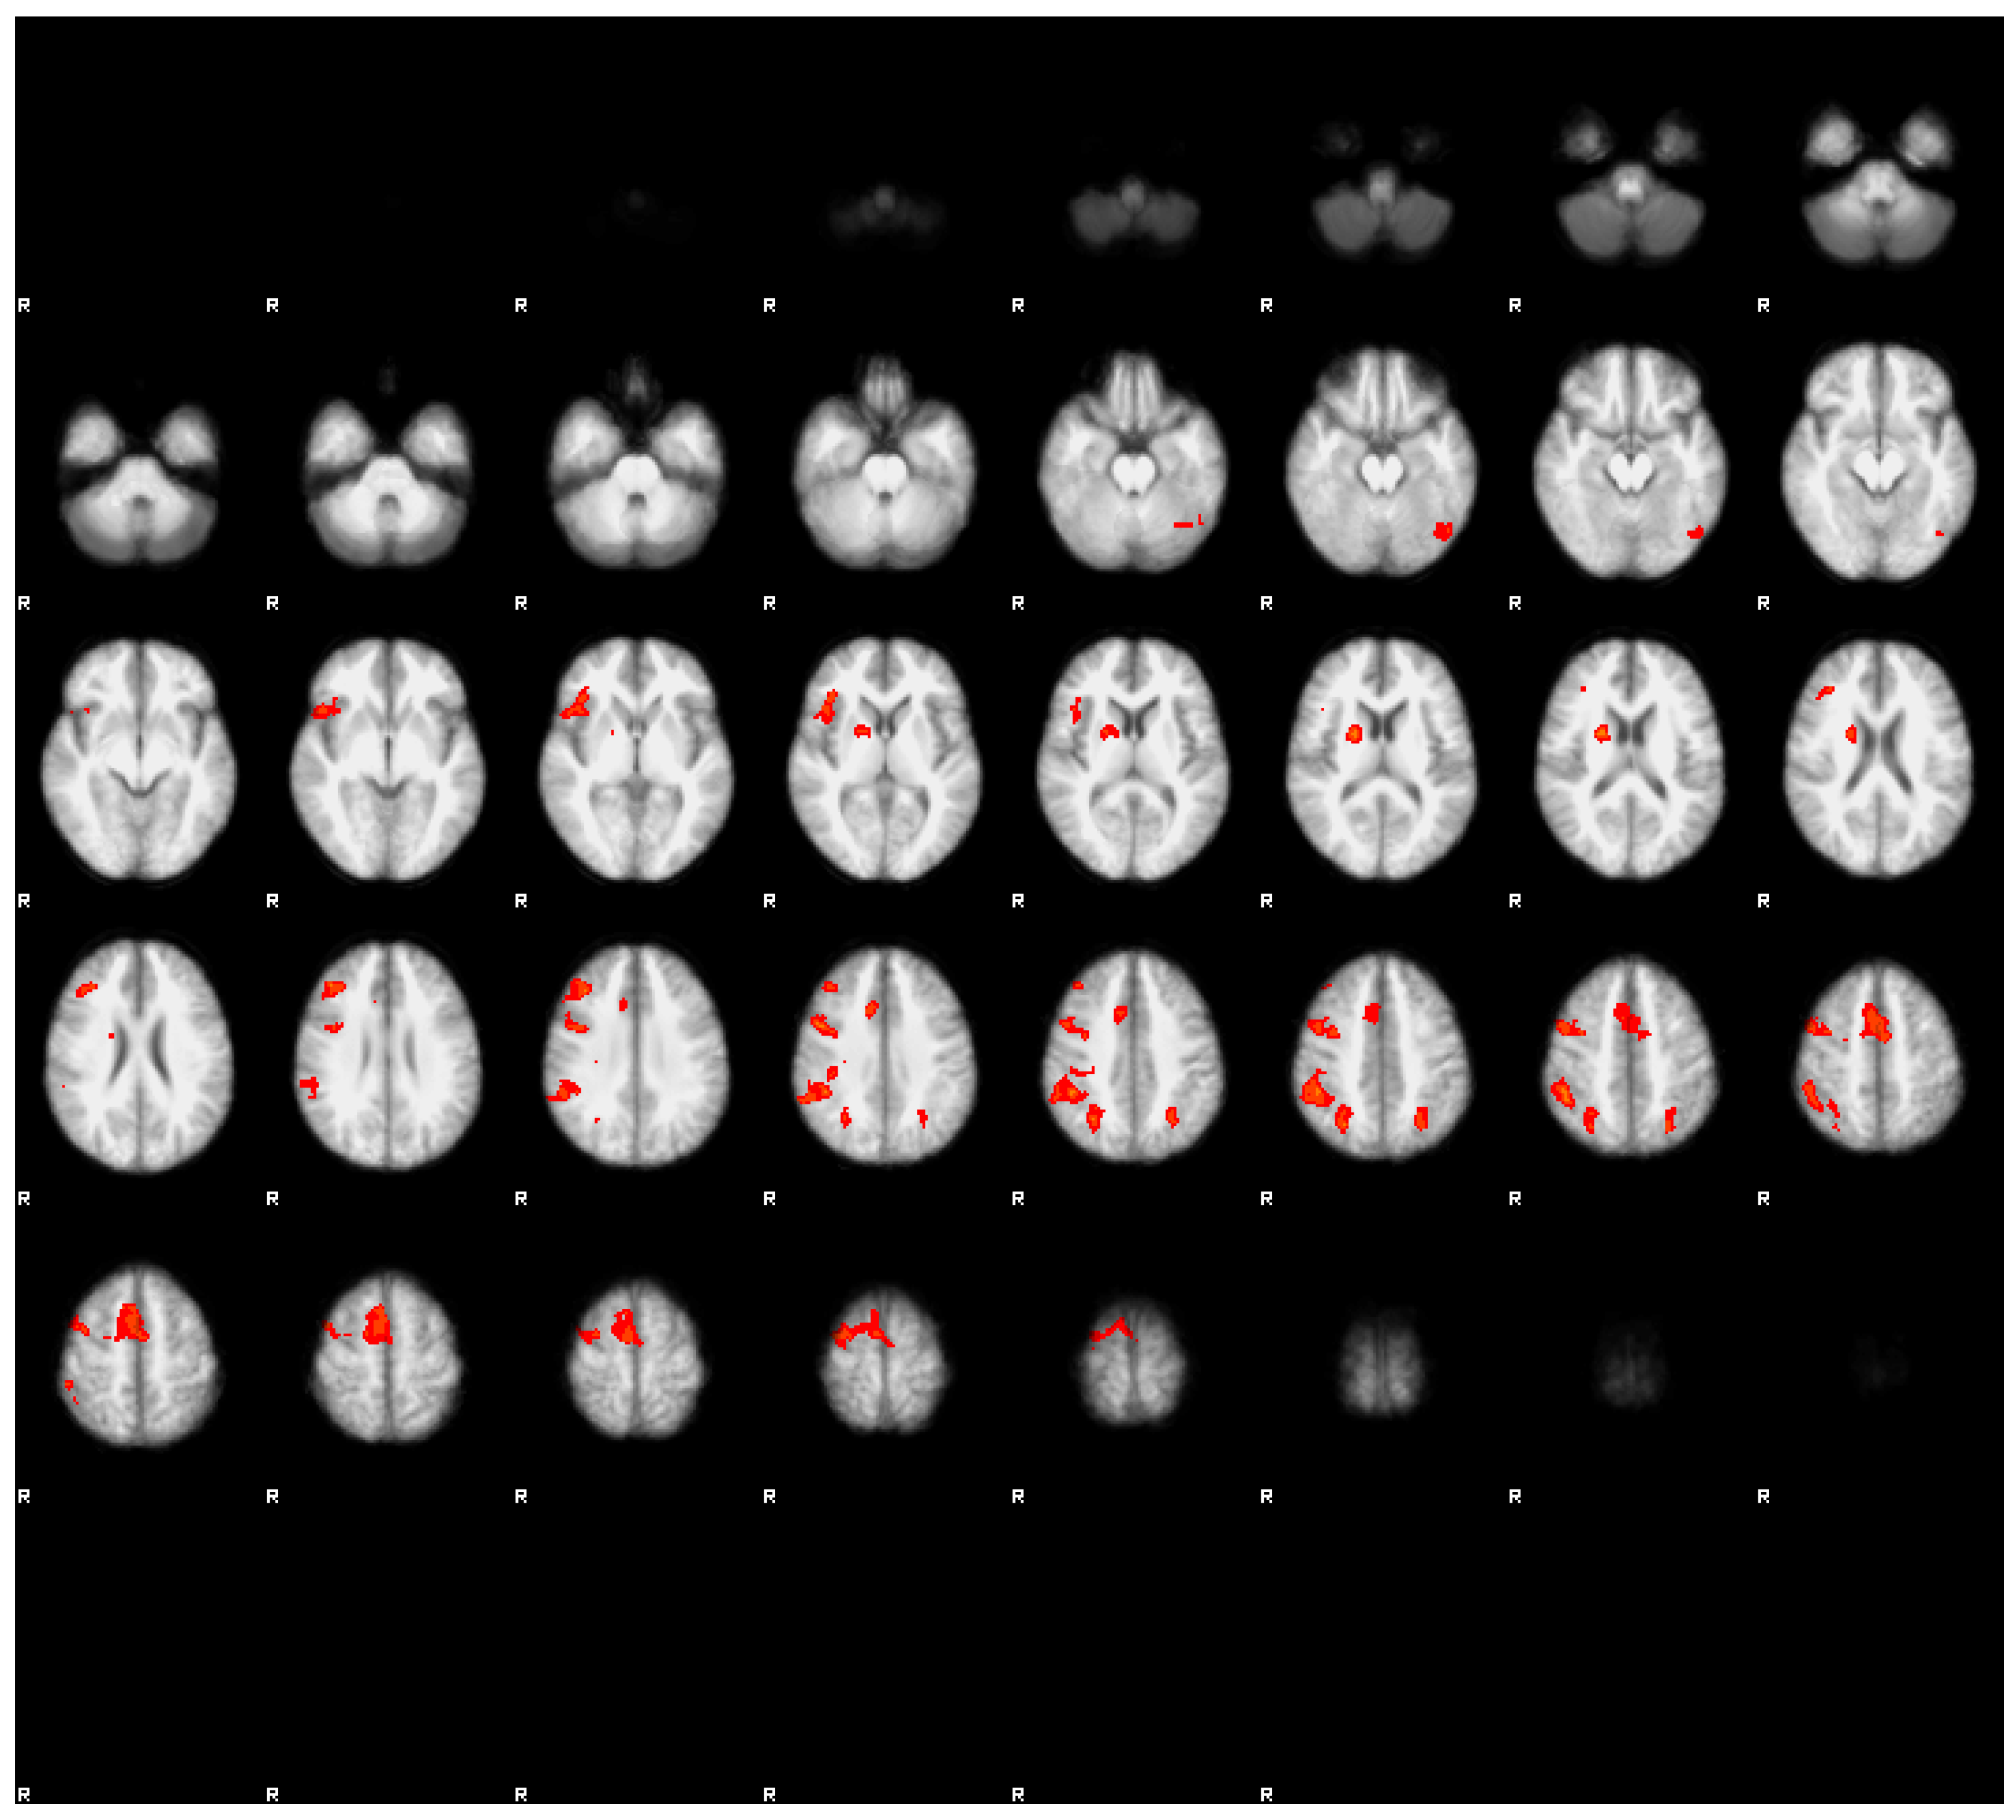

3.3.1. Main Effects of the Task in Both Conditions

The results are displayed in Figure 2 and Figure 3, as well as presented in Table 3 and Table 4. In both conditions, we observed a mostly overlapping pattern of activations in the lateral frontal, lateral parietal, and medial frontal regions. In both conditions, we also observed overlapping clusters in the left lateral temporo-occipital regions. There were marked differences between both conditions. In the rested condition, the general extent of suprathreshold activation was notably wider and more bilateral than in the fatigued condition. The strongest effects of task in the rested condition were observed in the posterior parietal cortex, as well as in the premotor cortex, extending into the dorsolateral cortex, mainly in the right hemisphere. Bilateral activations were also observed in the anterior insulae and in the medial frontal regions (SMA). In contrast with the fatigued condition, we observed bilateral activations in the polar visual cortex, as well as in the fusiform gyrus.

In the fatigued condition, the extent of the suprathreshold clusters was notably smaller. Bilateral activations were seen only in the parietal regions, while in the frontal regions, the activations were mainly observed in the right hemisphere. In neither condition were the activations correlated with the reaction times.

3.3.2. Contrast Results

Direct contrast between both conditions revealed a suprathreshold cluster only in the contrast fatigued > rested. The cluster was located in the right superior frontal gyrus (see Figure 4c). Interestingly, this region did not exceed the Z = 3.1 threshold in either condition, and it appeared in the fatigued > rested contrast because of the negative Z values in the rested condition (see Figure 4a showing the unthresholded Z values) and positive Z values in the fatigued condition (Figure 4b shows the unthresholded Z values). Thus, the difference of activation of this region in both conditions was caused by low response of this region in the rested condition and the moderately elevated response in the fatigued condition.

However, at the same time we observed a notable decrease of the extent of activation in the fatigued condition, indicating a less-consistent brain response to the experimental task across participants. Interestingly, we observed a more lateralized pattern of activation in the fatigued condition, with the majority of clusters located within the right hemisphere. We surmised that this effect might be associated with lowered brain metabolism in the state of sleep deprivation [22]. Of course, this does not mean that truck driver’s brain resembles a brain of a dolphin, yet it points to a lowered energy capacity of the fatigued brain, which can affect each hemisphere in a different manner [23]. The direct contrast between conditions revealed only one suprathreshold cluster, obtained in the fatigued > rested contrast. The reverse contrast did not reveal any significant differences. The cluster was located in the dorsal part of the prefrontal cortex. Interestingly, this region did not cross the significance threshold in any of the main effect contrasts for both the rested and fatigued conditions. However, a close inspection of the unthresholded images revealed that in the rested condition, this cluster was strongly deactivated, and in the fatigued condition, the response was positive, yet below the significance threshold. The inspection also revealed that the region discovered in the fatigued > rested contrast was a part of the larger cluster encompassing the medial frontal cortex—covering the SMA, pre-SMA, and parts of the superior frontal gyrus (see Figure 4). Previous research on the effects of cognitive working memory and attentional training research suggested that this region is a part of the cognitive control network, which is engaged in executive control over ongoing cognitive activity, and it is known that its responsiveness becomes significantly decreased over a training period [24,25]. Thus, in our case, the heightened activity of this region might suggest that a relatively simple task we used, involving simple visual feature conjunction detection, in the fatigued condition with lowered metabolic capacity due to sleep deprivation became a task that required more cognitive control resources in order to maintain the performance level. Thus, our results suggested that the influence in the arousal state of drivers on the cognitive level manifested as an increased demand for controlled attentional processing.

Figure 2. The main effects of the task in the rested condition. Images were thresholded at Z > 3.1. Note the extensive bilateral activation in the posterior parietal cortices, SMA, premotor cortex, and dorso-lateral prefrontal cortex. Activation in the middle temporal cortex was left-lateralized. The right side of the brain is denoted by letter R.

Figure 3. The main effects of the task in the fatigued condition. Images were thresholded at Z > 3.1. Note the more extensive activations in the right hemisphere of the brain (denoted by the letter R) in the posterior parietal cortices, supplementary motor area (SMA), premotor cortex, and dorso-lateral prefrontal cortex in comparison to the rested condition (see Figure 2). Activation in the middle temporal cortex maintained its lateralization in the left hemisphere.

Figure 4. Unthresholded Z-statistics image of rested condition results (a), unthresholded Z-statistics image of the fatigued condition results (b). Note the larger extension of activations in the rested condition (a) as compared to the fatigued condition (b). The region of statistically significant differences; i.e., the contrast fatigued > rested conditions thresholded at Z > 3.1 (c). The crosshairs indicate the same voxel at the center of the suprathreshold cluster in the right superior frontal gyrus (MNI coordinates: x = 18, y = 26, y = 56, cluster volume = 136, Z-score (maximum—4.53)).